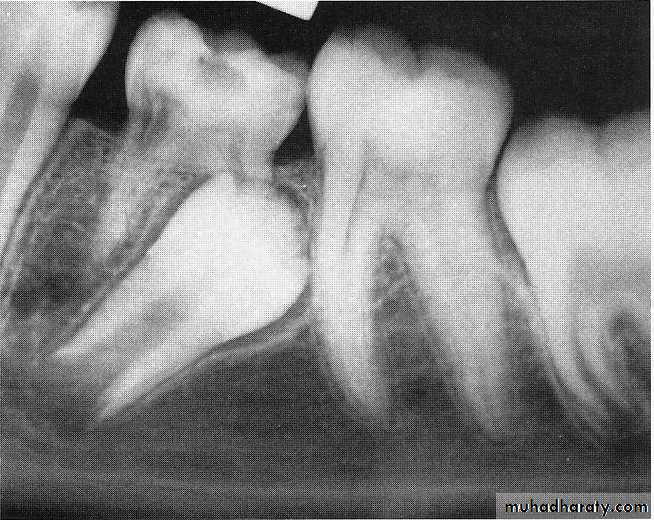

natal teeth (teeth present at birth)

neonatal teeth (teeth that erupt during the first 30 days)

85% of natal or neonatal teeth are mandibular primary incisors, and only small percentages are supernumerary teeth.

Early eruption of primary teeth seems to be familial.

A radiograph should be made to determine the amount of root developmentOne of the parents can hold the x-ray film in the infant's mouth during the exposure.

In some infants, however, the presence of such teeth may be a localized manifestation of an environmental cause or an underlying syndrome,and this underscores the importance of thorough diagnostic evaluations of infants with natal or neonatal teeth.

1. mobile to the extent that there is danger of displacement of the tooth and possible aspiration

2. sharp incisal edge of the tooth may cause laceration of the lingual surface of the tongue (Riga-Fede disease), and the tooth may have to be removed.

Most prematurely erupted teeth are hypermobile because of the limited root development.

in which case the removal of the tooth is indicated